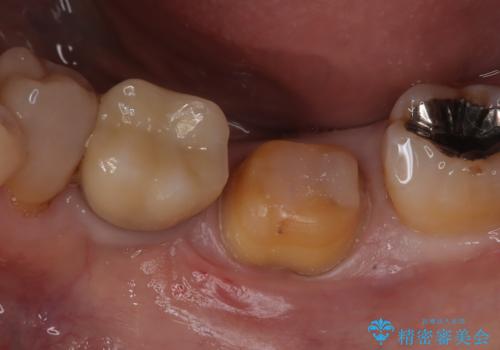

メタルインレーの下は。クラックラインを認めた歯。

- 定期検診にて、奥歯にクラックラインを認めました。

放置すると、抜歯になる可能性も高いため早めの治療を提案し、クラウンにて修復治療を行なっております。

術前説明にてクラックラインを認めることや治療の選択肢及び予後について理解していただいた上で、保存を希望されております。歯髄症状が出なかったため抜髄はせずに治療を完了しております。